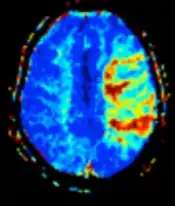

Perfusion weighted (PWI) Dynamic susceptibility contrastDSCMeasures changes over time in susceptibility-induced signal loss due to gadolinium contrast injection.[72]

• Provides measurements of blood flow

• In cerebral infarction, the infarcted core and the penumbra have decreased perfusion and delayed contrast arrival (pictured).[73]